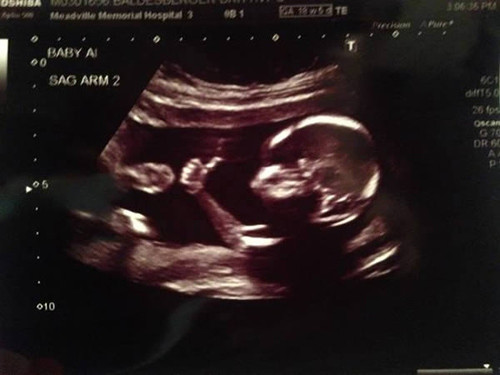

Một thành viên trang Reddit đã chia sẻ hình ảnh siêu âm em bé giơ ngón tay cái như ra hiệu ăn mừng trong bụng mẹ. Hình ảnh này ngay lập tức thu hút 2 triệu lượt người xem trong vòng 24h đồng hồ.